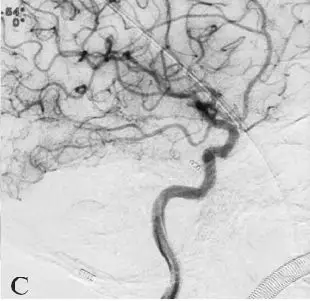

CT:头颅CT提示蛛网膜下腔出血,出血位于鞍上池、环池及侧裂池,双侧对称,无脑实质出血及脑积水表现,Fisher:分级2级(图18-1A)。

A:术前头颅CT;

图18-1变异原始三叉动脉动脉瘤患者术前CT及DSA影像